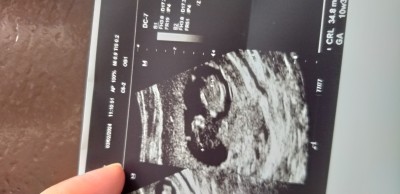

Nub ve ramz teorisinden anlayanlar cinsiyet yorumu yapabilir mi

Sorum başlıkta

Hakkında hayırlısı ama içime erkek dogdu teoriden anlamam valla

Teori çözmeye ne gerek var en yakin hastanenin kadin doğum doktoru ve 2 ay yeter size :D net sonuç için :D

Ben anliyorumda kendimde tutmadi o ayri :) kac haftalikken bu 7. Hafta olmasi gerekiyor

Kız bence bu

Erkek bence

Netleşince soylersin acaba doğru mu diye